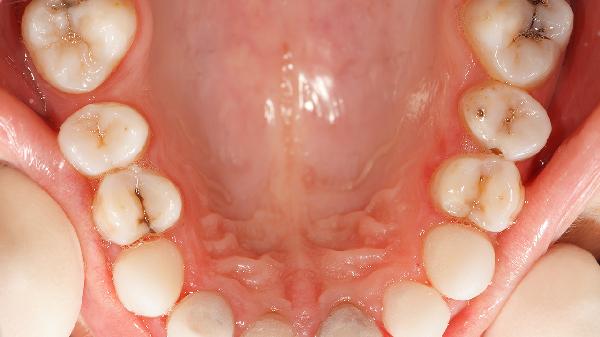

牙齒癢痛可能由牙齦炎、齲齒、牙周炎、牙齒過敏、牙髓炎等原因引起,可通過口腔清潔、藥物治療、脫敏治療、根管治療、手術(shù)治療等方式緩解。

牙齦炎通常與牙菌斑堆積有關(guān),表現(xiàn)為牙齦紅腫和輕微出血。日常可使用含氟牙膏刷牙,配合牙線清潔牙縫。若癥狀持續(xù),可遵醫(yī)囑使用復(fù)方氯己定含漱液或甲硝唑口腔粘貼片控制炎癥,避免發(fā)展為牙周炎。

齲齒造成的牙齒缺損會刺激牙神經(jīng)引發(fā)癢痛感,常伴隨冷熱敏感。早期齲齒可通過氟化鈉甘油糊劑局部涂抹修復(fù),中深度齲損需采用玻璃離子水門汀或復(fù)合樹脂填充。定期口腔檢查能及時(shí)發(fā)現(xiàn)齲洞。

牙周炎多由長期牙齦炎發(fā)展而來,可能出現(xiàn)牙齦萎縮和牙齒松動。除基礎(chǔ)潔治外,可配合使用鹽酸米諾環(huán)素軟膏局部給藥,嚴(yán)重者需進(jìn)行牙齦翻瓣術(shù)。吸煙會加重病情,建議戒煙。

牙本質(zhì)暴露會導(dǎo)致冷熱刺激敏感,與牙齦退縮或過度刷牙相關(guān)??蛇x用含硝酸鉀的舒適達(dá)抗敏牙膏,或由醫(yī)生實(shí)施氟保護(hù)漆脫敏治療。避免食用過酸食物防止牙釉質(zhì)進(jìn)一步磨損。

齲齒或外傷引發(fā)的牙髓感染會產(chǎn)生放射性疼痛,夜間可能加重。急性期需開髓減壓,后期行根管治療清除壞死組織。布洛芬緩釋膠囊可短期緩解疼痛,但需及時(shí)就醫(yī)避免頜骨感染。

保持每日兩次巴氏刷牙法清潔牙齒,每年進(jìn)行口腔檢查和潔治。選擇軟毛牙刷避免牙齦損傷,使用沖牙器輔助清潔牙菌斑。出現(xiàn)持續(xù)疼痛、牙齦化膿或牙齒松動時(shí)須立即就診,延誤治療可能導(dǎo)致牙齒脫落。孕婦、糖尿病患者等特殊人群更需重視口腔衛(wèi)生管理。